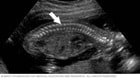

My baby wouldnt open its hands in my ultrasound. Ultrasound linear transducer is placed parallel to the lateral aspect of the infants hip. Fetal clenched hands are an antenatal ultrasound observation where the fetal hands are in a constant permanently clenched position as if being unable to extend.

If your baby is sleeping during the appointment you wont. In this prospective study 100 second trimester fetuses were assessed to determine the frequency of visualization of the open fetal hands and the three phalanges of the fifth digit during a routine ultrasound examination. That is the first question a coworker asked my husband when he returned to work following our 20-week anatomy scan.

The next ultrasound last week hand where wide open and the other marker disappeared. The ultrasound technician will be looking for physical abnormalities on the baby checking the location of the placenta and measuring your babys growth. A prospective type 1 cohort study was conducted in a tertiary prenatal.

Babys first ultrasound phoenixs premier 4d 5d hd live ultrasound center open 7 days a week from 9am to 9pm same day appointments 602 478-0806 Toggle navigation. Second-trimester anomaly scan was introduced as a regulated practice in Romania in 2019 causing misperceptions and unrealistic expectations about this examination among pregnant women. Open right hands were seen in 82 82 fetuses and the three phalanges of the right fifth digit were seen in 71 71 fetuses. When Lyndon later shared this I. An ultrasound which is also called a sonogram is a noninvasive test that uses sound waves to create images of your baby uterus and placenta. Ultrasound showing boy babyin this video there is an intrauterine viable fetus with the arrow pointing to the external genetalia that shows male boy gende. The next ultrasound last week hand where wide open and the other marker disappeared. At 8 weeks of development the fetus is very small. A prospective type 1 cohort study was conducted in a tertiary prenatal.